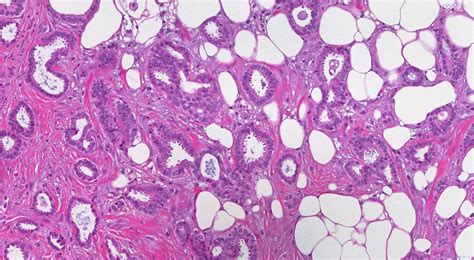

So, first things first, what is Invasive Ductal Carcinoma (IDC) ? Think of it as the most common type of breast cancer, guys. It starts in the milk ducts of the breast – those little tubes that carry milk to the nipple. The key word here is ‘invasive’ . This means the cancer cells have broken out of the duct and started to invade the surrounding breast tissue. Unlike ‘in situ’ cancers (like DCIS, which stands for Ductal Carcinoma in Situ), which are contained within the duct and haven’t spread, IDC has the potential to travel. And when we say travel, we mean through the bloodstream or the lymphatic system. This invasiveness is what allows it to potentially spread to other parts of the body, making it a more serious diagnosis. It often feels like a lump, but not always. It can be detected through mammograms and other imaging tests. The cells themselves, under a microscope, look like they’ve escaped their original confines and are growing into new territory. It’s pretty wild to think about, but understanding this basic mechanism is foundational to grasping the whole picture of breast cancer progression. Most breast cancers diagnosed are IDC, so even though it’s common, it’s still a big deal and warrants serious attention and comprehensive care. The histology, or the study of the tissues, plays a massive role in confirming IDC and determining its grade, which gives us clues about how aggressive the cancer might be and how quickly it might grow and spread. This detailed examination is a critical part of the diagnostic process, ensuring the right treatment plan is put into action from the get-go.